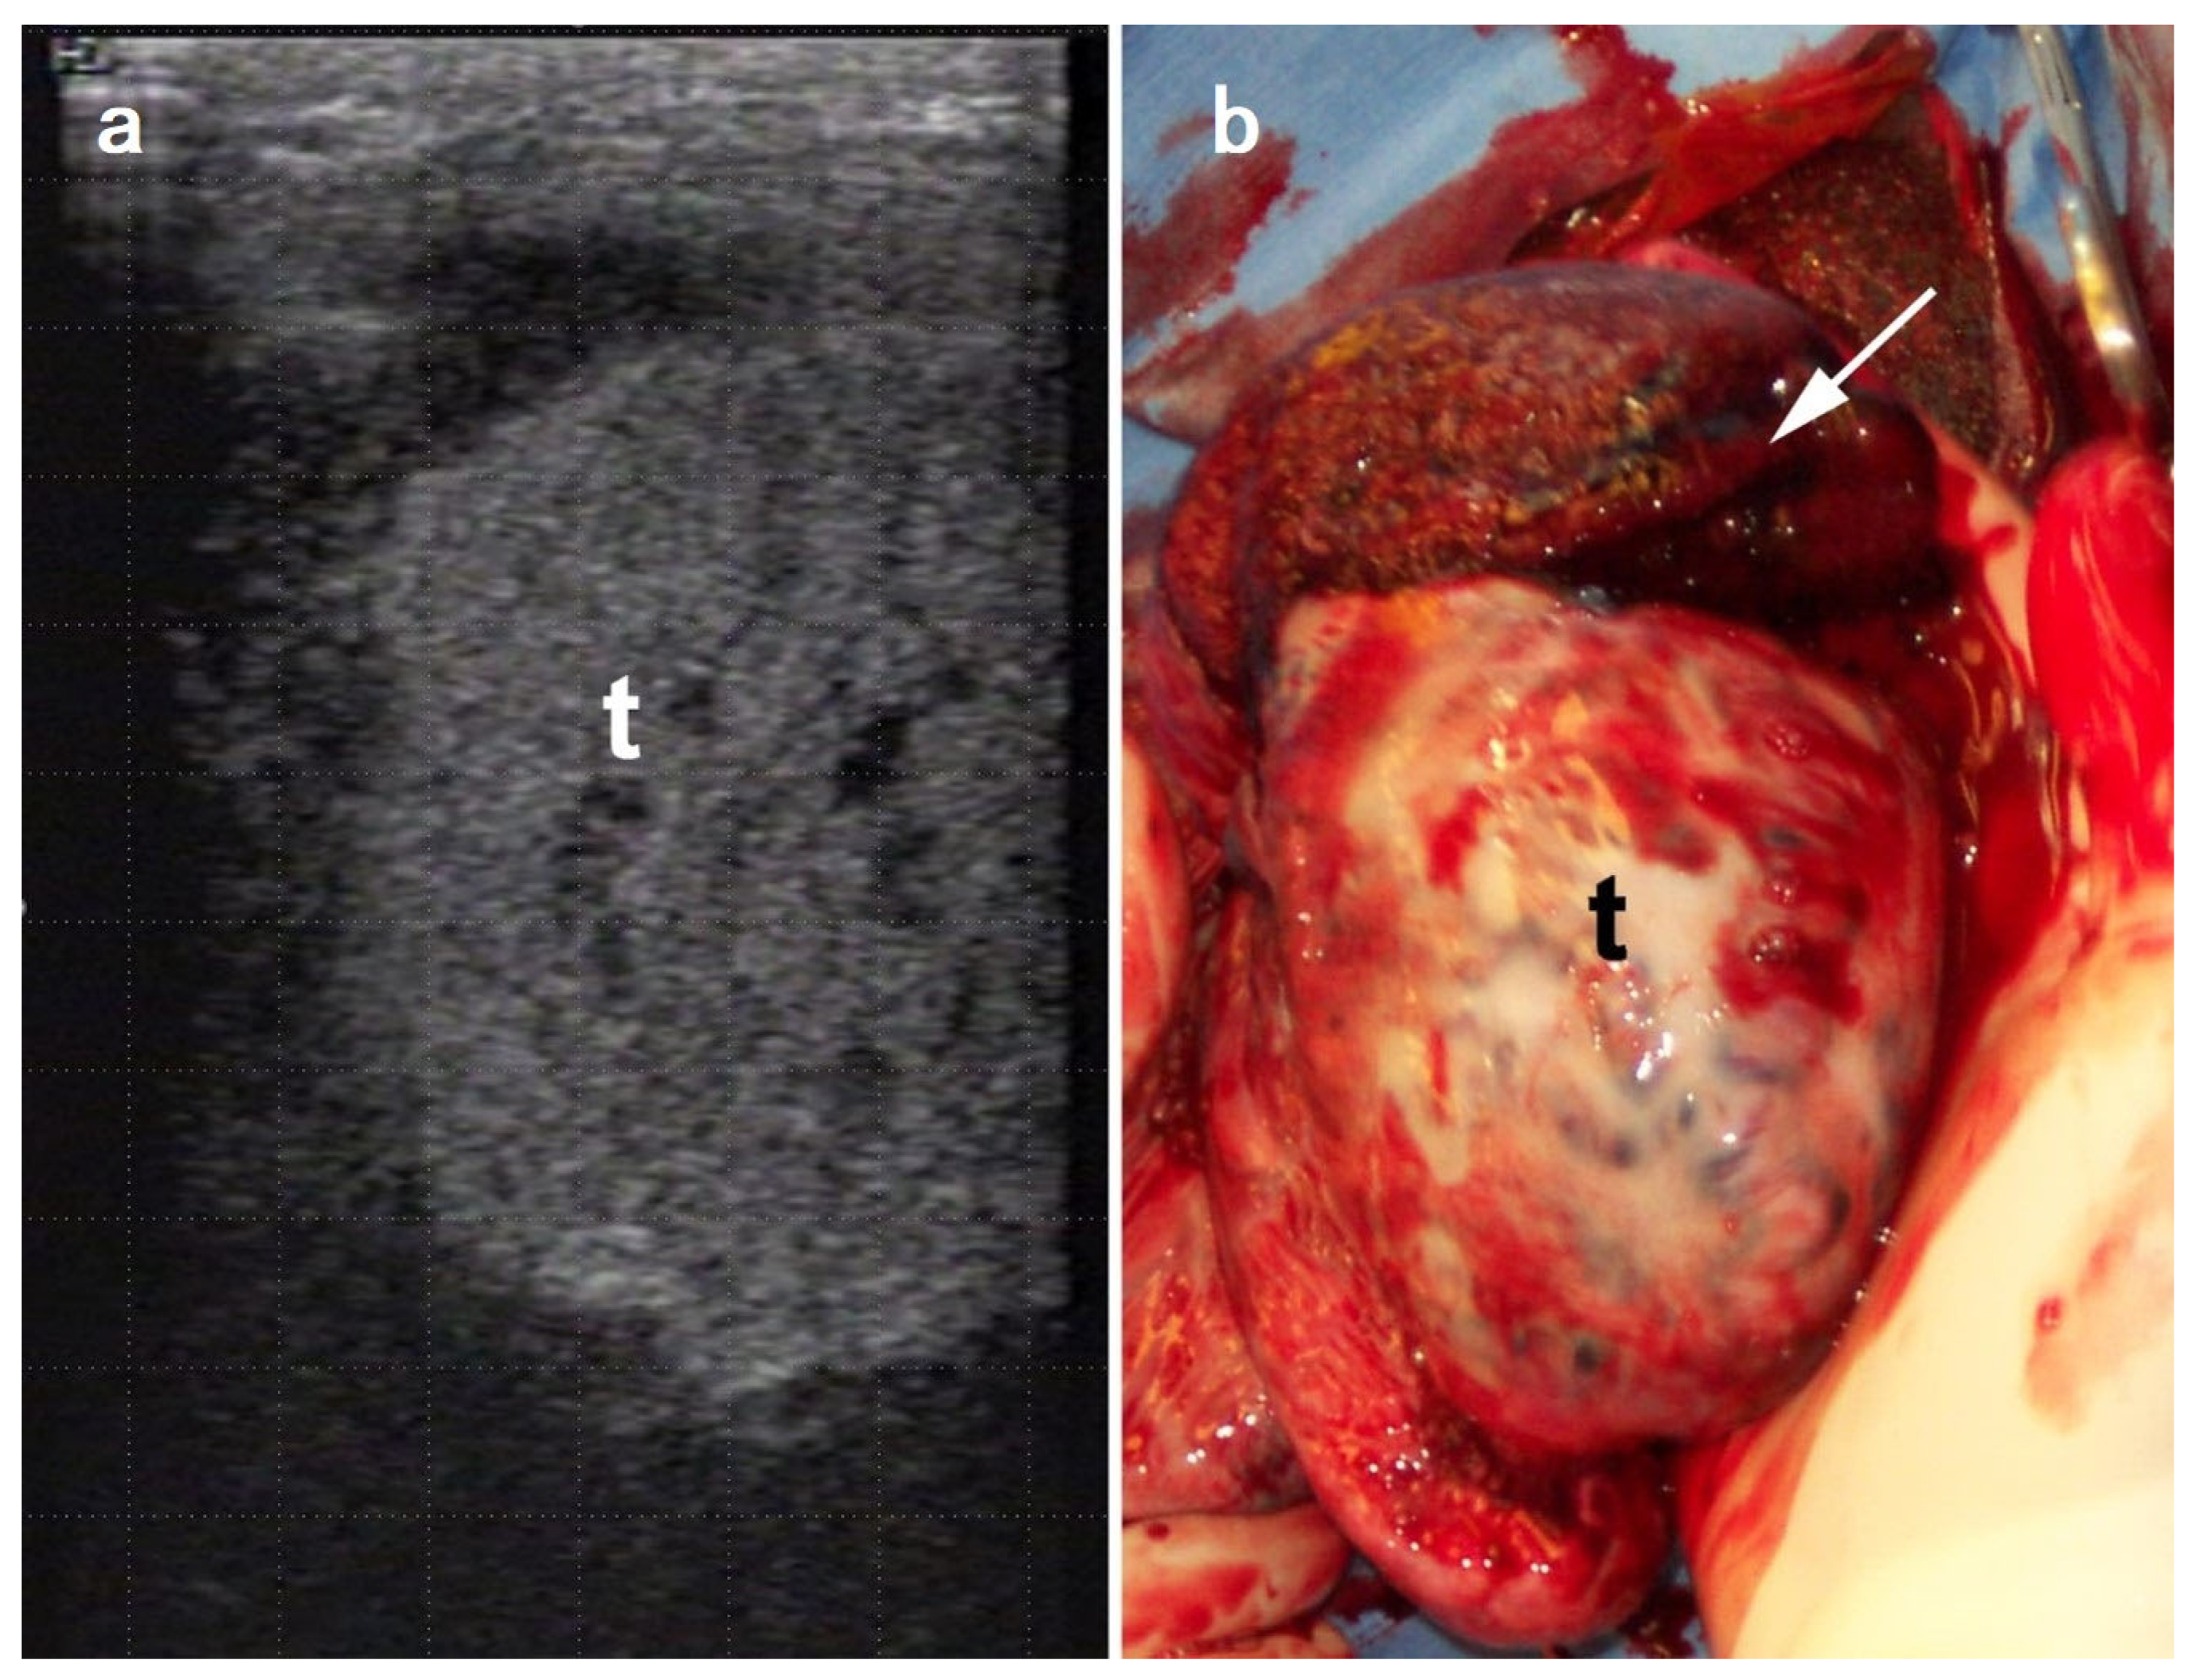

5.4. Scrotal and Testicular Tumors